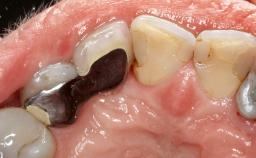

Surgical Management of Peri-Implantitis: Removal of Implant Due to Recurrent Infection Using an Implant-Retrieval Tool

Despite anti-infective surgical treatment, some patients may experience recurrent infection and progressive bone loss requiring additional treatment. This case describes a conservative approach using an implant retrieval tool without the need for excessive bone removal or use of a trephine.

A 65-year-old female patient was referred to the periodontist for assessment and management of infection associated with an implant at site 12. The general dentist had noted suppuration on probing during examination.